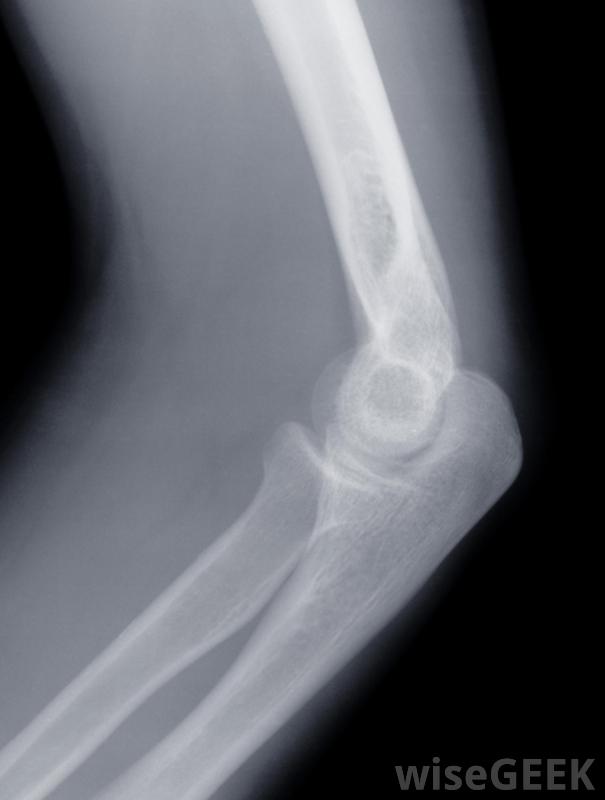

服用消炎药治疗膝关节肿胀和疼痛可以显著改善这种状况。这些药物可以在柜台购买,也可以由医生处方。此外,膝盖肿胀和疼痛可能会对冰敷和腿部抬高产生反应。此外,膝关节肿胀的常见原因疼痛包括膝盖挫伤、瘀伤、软骨撕裂和关节炎在制定治疗计划之前,做出正确的诊断是很重要的。如果抗炎药和冰袋不能产生效果,医生需要得到通知,以便进一步确定病因。医生可能会建议进行x光检查,甚至可能会对膝关节进行抽吸,以确定是否有液体存在。有时,膝盖受伤会促进液体的生成。在这种情况下,定期排出液体可能会缓解膝盖肿胀和疼痛膝盖的示意图。导致膝盖肿胀和疼痛的另一个原因是痛风。虽然痛风通常发生在较小的关节,如大脚趾和肘关节,但其他大关节,如膝盖也会受到影响。要诊断痛风,医生需要进行尿酸血检一般来说,当血液中尿酸浓度过高时,就会出现痛风。痛风的症状可以模仿关节炎的症状,如关节疼痛、肿胀和发红。此外,还可能出现活动受限和活动范围受限的情况膝盖受伤可能导致膝盖疼痛和肿胀。通常建议休息腿部以减轻膝盖肿胀和疼痛。长时间站立并对膝盖施加压力可能会恶化肿胀和增加疼痛。虽然加热垫可以缓解膝关节疼痛,但不建议使用,因为热会促进肿胀并进一步增加疼痛。当膝盖问题变得慢性时,借助拐杖行走有时可以通过承受腿部重量来减轻膝关节肿胀和疼痛在极少数情况下,当保守的止痛方法无法缓解膝盖肿胀和疼痛时,手术可能是有必要的。膝关节疼痛和肿胀的手术类型取决于引起这种情况的原因。如果症状与软骨有关,则应进行手术移除受伤软骨。如果存在骨刺,移除它们也可以缓解症状。如果膝盖骨因受伤而骨折,则应进行手术修复它可能是唯一的选择,彻底的外科会诊可以为病人提供选择,因此他和他的医生可以决定哪种治疗是合适的抗炎药通常对膝关节疼痛有效。